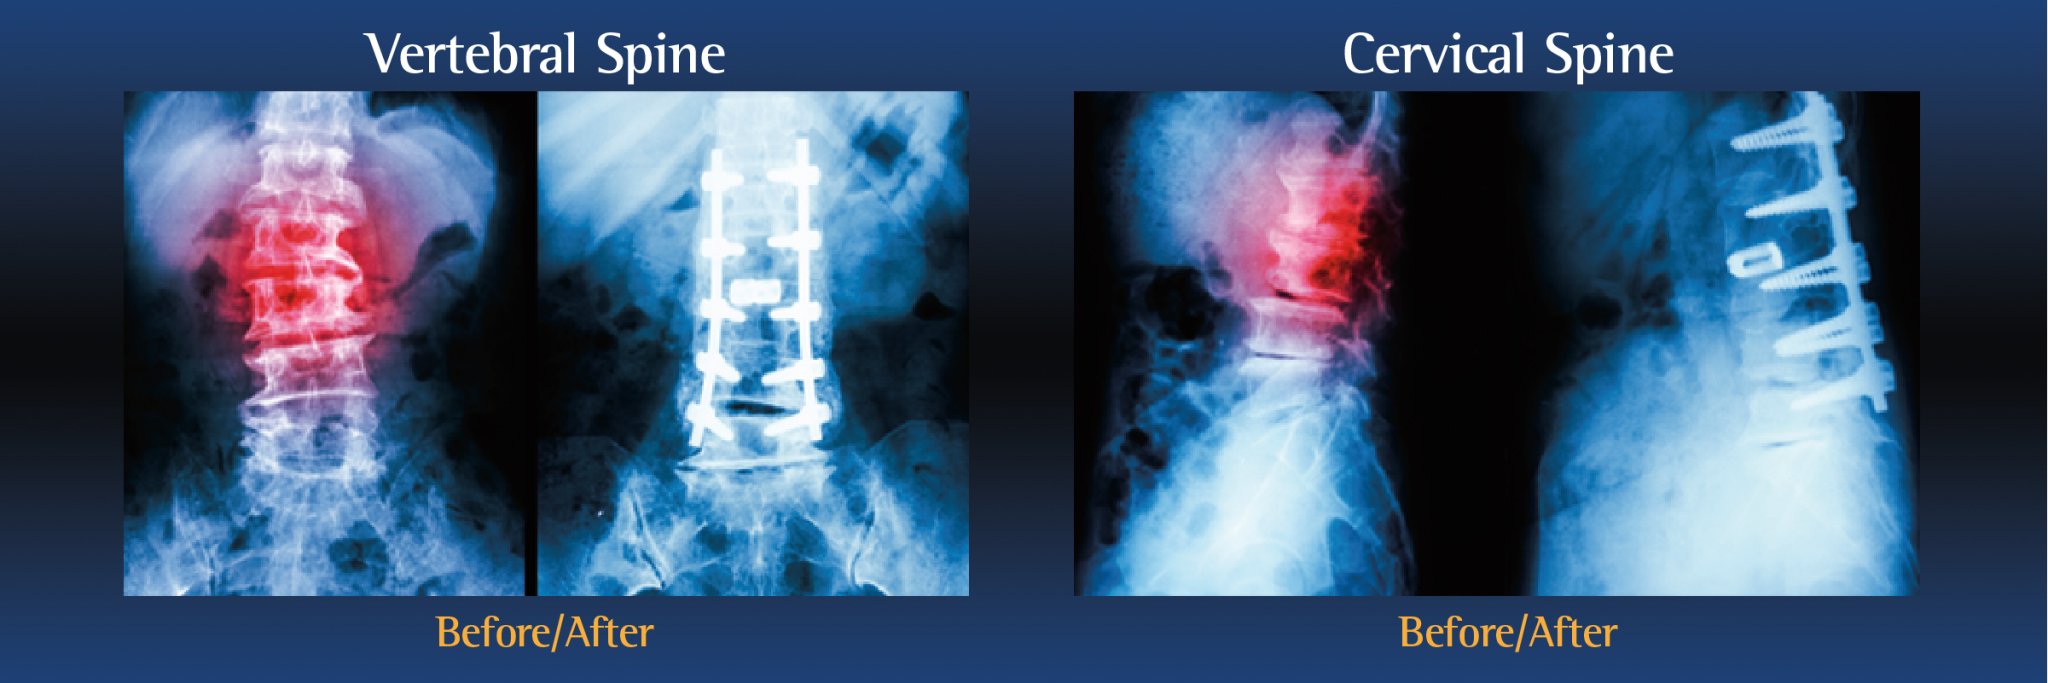

Types of spinal fusion surgery

There are several types of spinal fusion surgery. The type of procedure performed will depend on the patient’s individual condition, as well as the location of the pain:

- Cervical Fusion is performed on the neck

- Lumbar Fusion is performed on the lower back

During the operation, an incision is made in the neck, back or abdomen. Bone, debris, bone growths, lamina, and/or the damaged vertebral disc may be cleared from the spine, creating more space and relieving pressure on the spinal nerves. The surgeon will then take the proper steps to correct the patient’s specific problem.

Bone grafts may then be placed in the space or along the side of the spine. If additional support is needed, metal hardware (including pins or screws), may be used to steady the spine as it fuses. The incision is closed to finalize the surgery.

The grafts will grow into solid bone, fusing together the vertebrae. Patients may have to wear a back brace post-surgery, which will support your spine and keep the vertebrae from moving as the grafts fuse together.